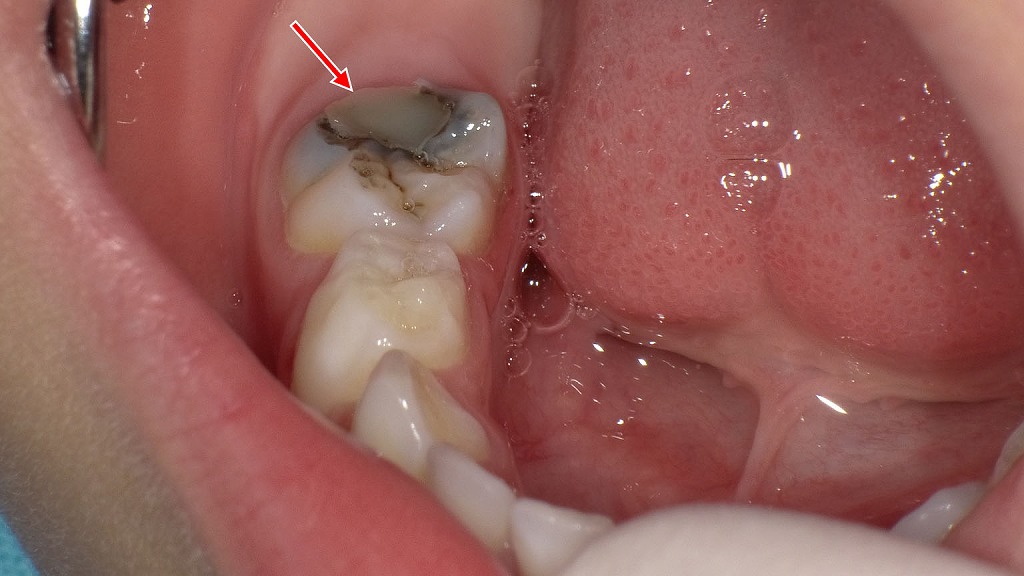

3歳児の下顎第二乳臼歯に認められた虫歯の症例です。奥歯の溝は深く、歯ブラシが届きにくいため、乳歯の時期は特に虫歯リスクが高くなります。本症例ではサホライド塗布後にレジン充填を行い、進行抑制と形態回復を図っています。このように虫歯になりやすいお子さんでは、溝をあらかじめ封鎖するシーラントが予防処置として効果的です。